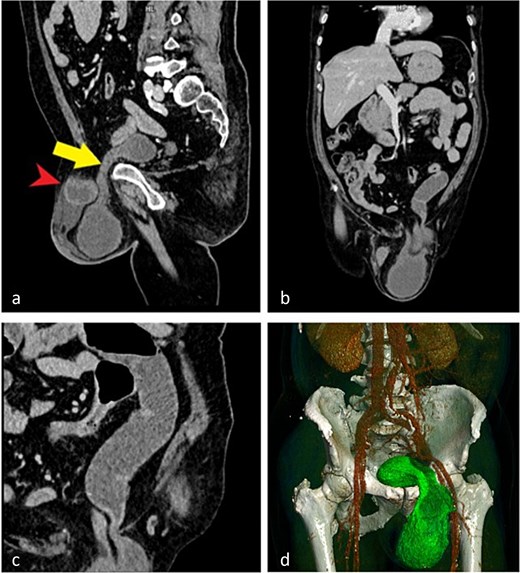

Computed tomography (CT) demonstrated an incarcerated left inguinoscrotal hernia containing a portion of the urinary bladder, a small bowel loop, and free fluid within the hernial sac (Fig. 1).

CT images demonstrating an incarcerated left inguinoscrotal hernia. (a) Sagittal plane showing herniation of the anterior bladder wall and a small bowel loop. (b) Coronal plane view of the herniated portion of the urinary bladder and small bowel. (c) Dilated small bowel loop with an air–fluid level proximal to the site of obstruction. (d) Three-dimensional reconstruction illustrating the herniated bladder.